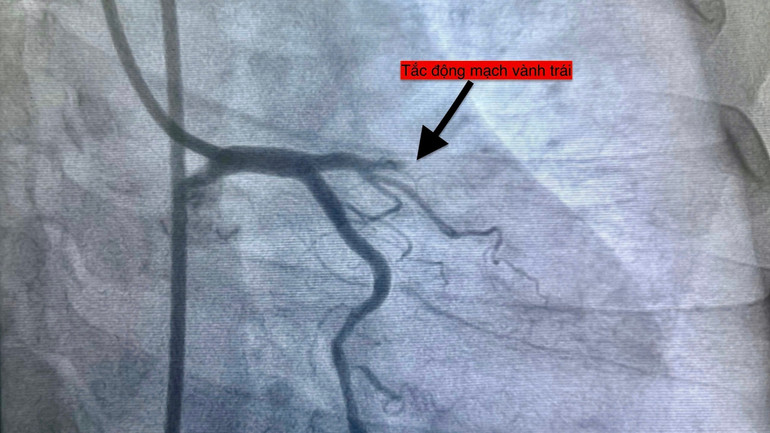

Bệnh viện đa khoa khu vực Thủ Đức vừa ghi nhận liên tiếp bốn ca nhồi máu cơ tim cấp chỉ trong 24 giờ ngày 14/11, một dấu hiệu đặt ra cảnh báo quan trọng về mối liên hệ giữa biến động thời tiết và sức khỏe tim mạch.

Điểm đáng chú ý khi trong nhiều tháng trước đó, Bệnh viện đa khoa khu vực Thủ Đức chỉ tiếp nhận trung bình hai ca mỗi tuần nhưng riêng hai tuần đầu tháng 11, số bệnh nhân nhồi máu cơ tim cấp đã tăng thêm tám ca và ngày 14/11 trở thành ngày có số ca cao nhất từ trước đến nay.

Bốn bệnh nhân với độ tuổi từ 51 đến 78, thuộc nhiều nhóm nguy cơ khác nhau đều nhập viện trong tình trạng cấp cứu và được can thiệp mạch vành kịp thời.

Hiện tượng bốn ca liên tiếp trong một ngày là dấu mốc cảnh báo, cho thấy áp lực đang gia tăng lên hệ thống y tế trong bối cảnh thời tiết bất thường. Qua việc can thiệp kịp thời cứu sống các ca bệnh, Bệnh viện đa khoa khu vực Thủ Đức cho thấy năng lực cấp cứu tại đây.